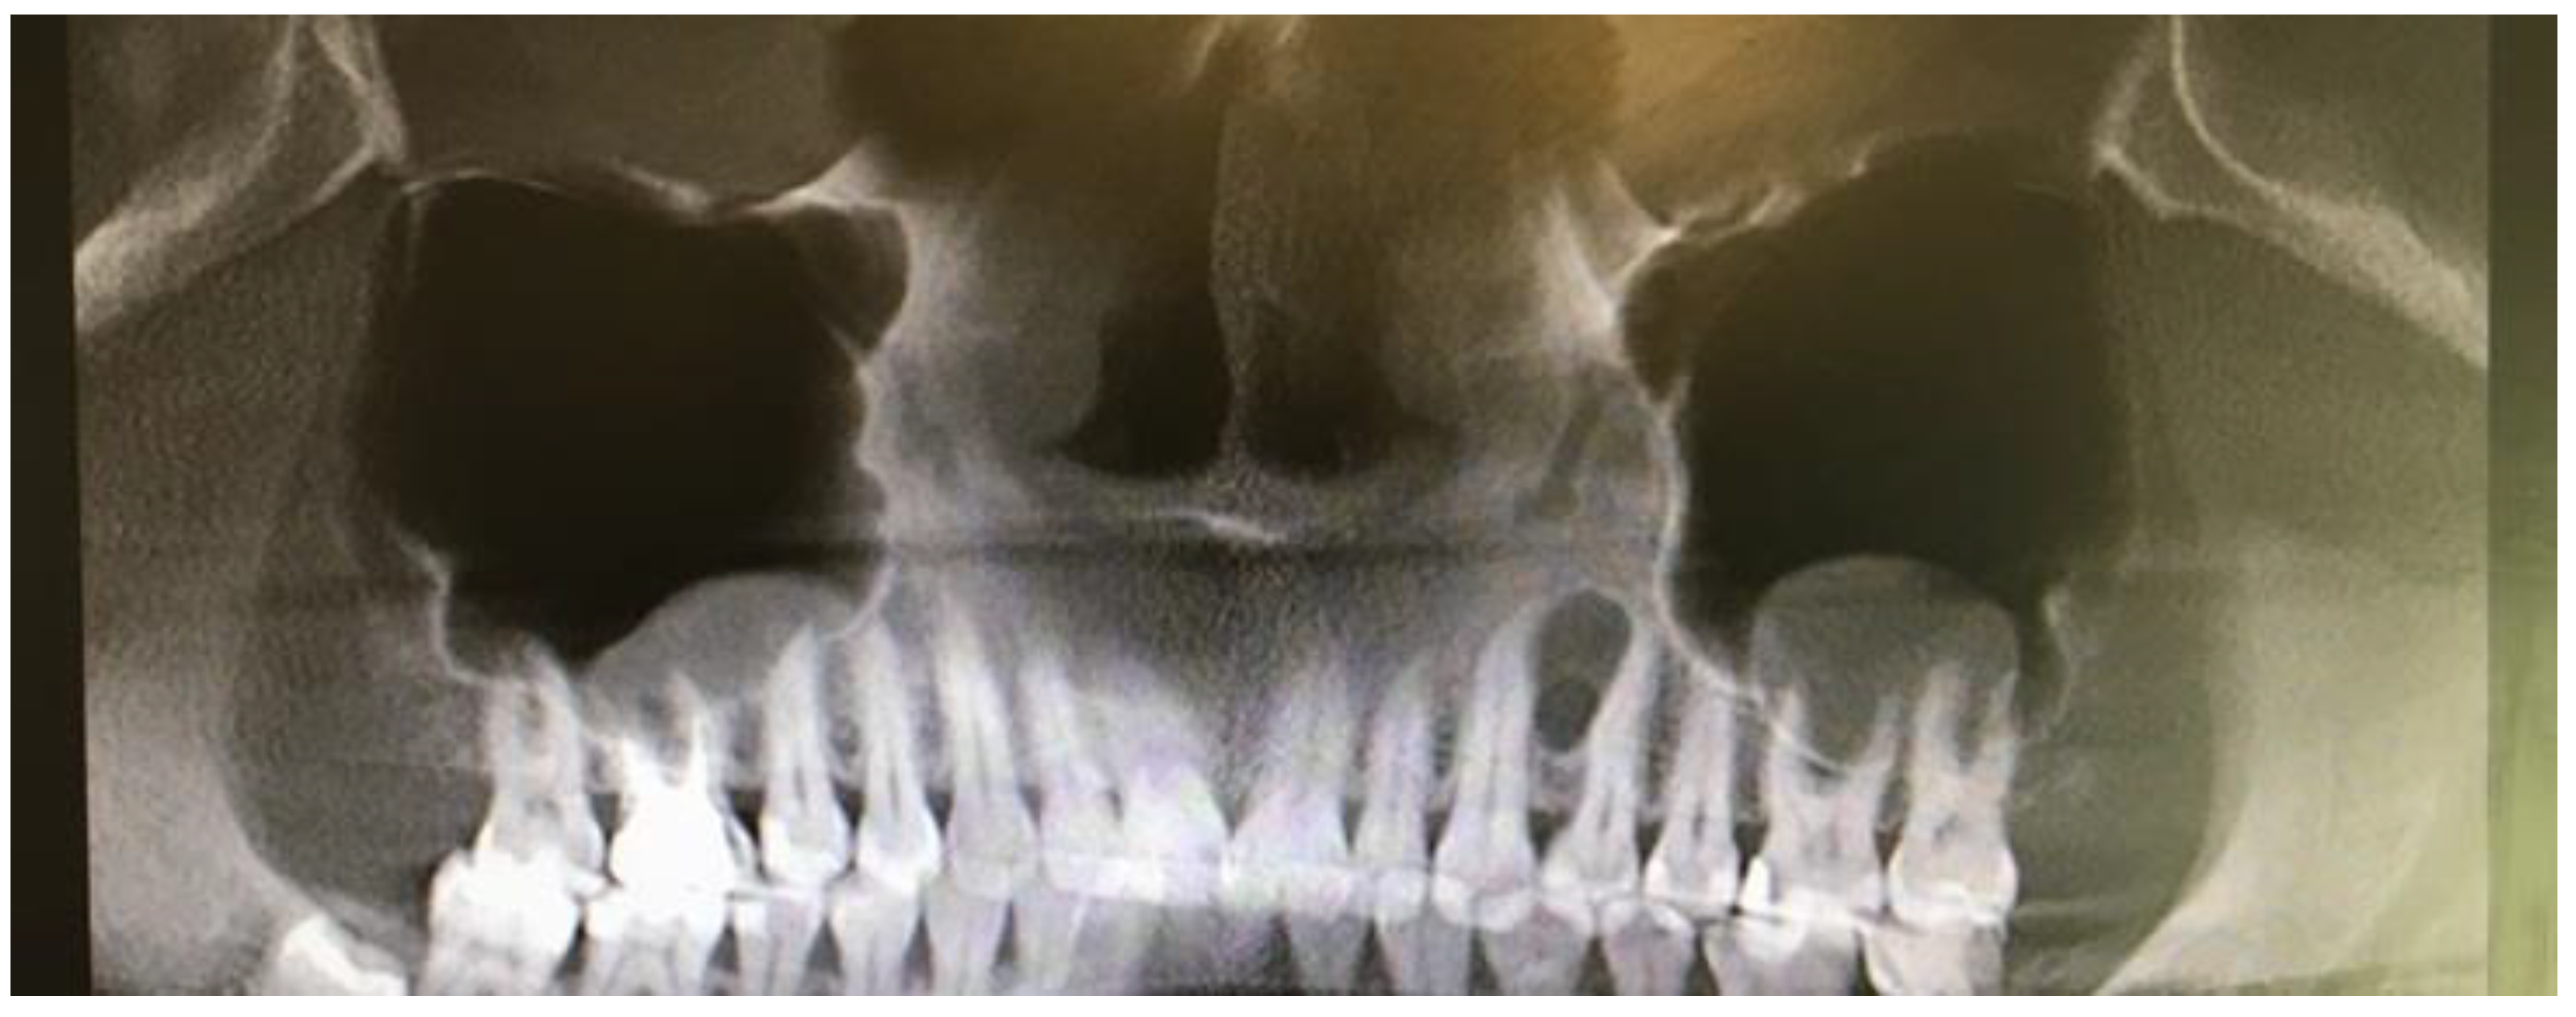

A 35-year-old female patient presented with a small, well-defined lesion on the attached gingival area, approximately 5/6 mm in diameter between roots of teeth 23–24, reported to the Privat Dental Clinic. The patient’s main concern was focused on gingival asymmetry and a tumor-like mass, painless and sometimes tender on tooth brushing. Clinical anamnesis revealed the occurrence of this asymptomatic mass for over 6 months. Because of swelling and atypical cortical expansion, the patient was referred for consultation and treatment. The patient was generally healthy without any chronic illness or important medical and dental past. A routine panoramic radiograph revealed a well-defined, radiolucent, left maxillary lesion located between the roots of the canine and first maxillary premolar (Figure 1 and Figure 2).

Figure 1. Panoramic radiograph slice from CBCT evaluation of LPC.